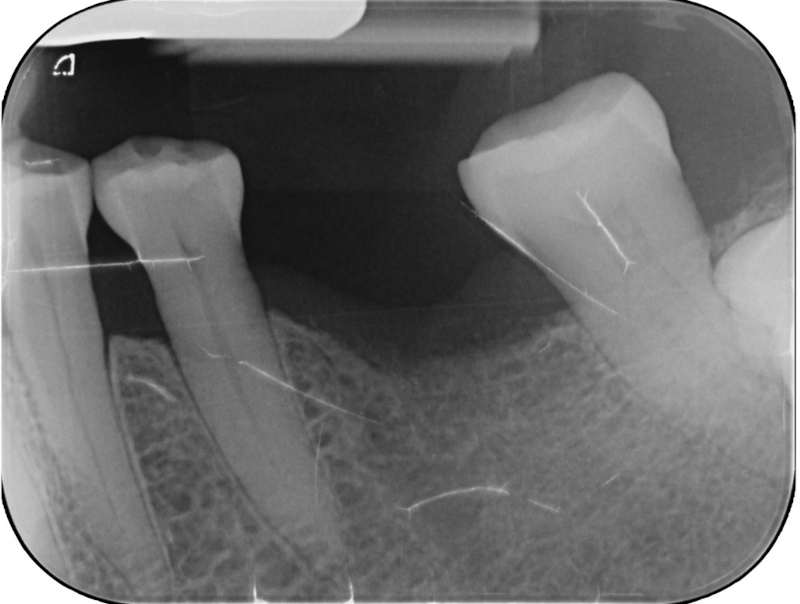

Fig. 1: Radiograph of the single edentulous site in the region of tooth #36 requiring restoration.

Patient assessment and initial situation A 62-year-old female patient presented with a single edentulous site in the mandibular left first molar region (tooth #36; Fig. 1). The missing tooth had been extracted six months previously owing to a vertical root fracture. The patient was in good general health and expressed a desire for rapid and minimally invasive implant-supported rehabilitation. Clinical and radiographic evaluation confirmed sufficient bone volume and soft tissue to allow placement of a standard diameter implant without requiring regenerative procedures.